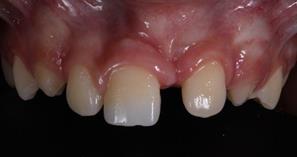

In the following session, direct restoration of the upper right central incisor was performed with MCR (Vittra APS Unique) (FGM Dental Group, Joinville-SC, Brazil). In this occasion, considering the extent of the fracture, a silicone matrix (Perfil, Coltene, Rio de Janeiro-RJ, Brazil) was used to restore the palatal face. The restorative clinical sequence covered: 1) Infiltrative anesthesia, with 2% mepivacaine (adrenaline vasoconstrictor 1:100,000), to remove the GIC, with a #2 Jet carbide drill (Labordental, São Paulo-SP, Brazil), mounted at low speed handpiece; 2) Finishing the enamel in the cavo-surface angle, with diamond tip #1190F (Kavo, Joinville-SC, Brazil); 3) Prophylaxis of the anterior superior teeth with pumice paste and water, with the aid of a Robson brush (Ultra-soft, American Burrs, Palhoça-SC, Brazil); 4) Modified rubber dam isolation; 5) Acid etching of enamel and dentin with 37% phosphoric acid (Biodinâmica, Ibiporã- PR, Brazil), for 30 seconds on enamel and 15 seconds on dentin; 6) Rinsing with a water jet to remove the conditioning agent, for 30 seconds; 7) Drying the operative field with an air jet and the conditioned dentin, with a paper filter (Melitta, São Paulo-SP, Brazil); 8) Application of two layers of the adhesive system (AS) (Adper Single Bond 2, 3M ESPE, Sumaré-SP, Brazil), with the aid of a micro-applicator brush (Cavibrush regular, FGM, Joinville-SC, Brazil), actively, for 15 seconds; 9) Removal of excess AS with the aid of a clean micro-applicator brush and time interval for solvent evaporation; 10) Light cure of the AS with a Radii-Call- SDI device (Southern Dental Industries, São Paulo- SP, Brazil), with an irradiance of 1200 mW/cm2, for 20 seconds; 11) Positioning of the silicone matrix (Figure 3) to restore the palatal face, based on the insertion of the MCR Vittra APS Unique (FGM Dental Group, Joinville-SC, Brazil), and light cure with the LED-based device; 12) Using the incremental technique, with the aid of an insertion spatula and brush, the area corresponding to the dentin was restored with MCR Vittra APS Unique (FGM Dental Group, Joinville-SC, Brazil) with characterization of the volume and anatomy (grooves development) of this substrate (Figure 4). MCR was also inserted over the cavo-surface angle to mask the

transition line between the tooth and the restored area until the entire buccal surface was completed. All CR increments were light-cured for 40 seconds; 13) Immediate finishing of the proximal surface with a #12 scalpel blade (Feather Safety Razor, Osaka, Japan), on the palatal surface with multi-bladed drill #9406 (Microdont, São Paulo-SP, Brazil) and on the buccal surface with sanding discs (Diamond Master, FGM Produtos Odontológicas, Joinville-SC, Brazil) (Figure 5).

After a week, the characterization (texturing) of the buccal surface was carried out using diamond-coated (No. 3195F, KG Sorensen) carbide burs (No. 9714 FG, Microdont), silicon impregnated polishers and brushes (Jiffy polishers, Ultradent Products), and a felt disc (Diamond Flex, FGM Dental Group) in association with an aluminum oxide-based polishing paste (Diamond R, FGM Dental Group). The patient underwent clinical and radiographic follow-up sessions after 1 month, 6 months and 10 months (Figures 6 and 7), when, considering his age and need for multidisciplinary intervention, he was referred to the Integrated Children's Clinic for treatment of the upper left central incisor, which was impacted and had no space for eruption. The orthodontic

In a clinical case of tooth fracture, the manufacturer of the MCR recommends the insertion of a body CR to restore the palatal face, prior to the insertion of the MCR increments, to support the color. However, in the reported case, considering the CR volume, in bucco-palatal thickness, it was decided to insert only the MCR to restore saturation, opacity and color perception. After 10 months of follow-up, considering the criteria: color, adaptation and marginal pigmentation, polishing and surface texture, fracture, secondary caries and sensitivity,16 the treatment performed demonstrates satisfactory aesthetic, biological and functional results.